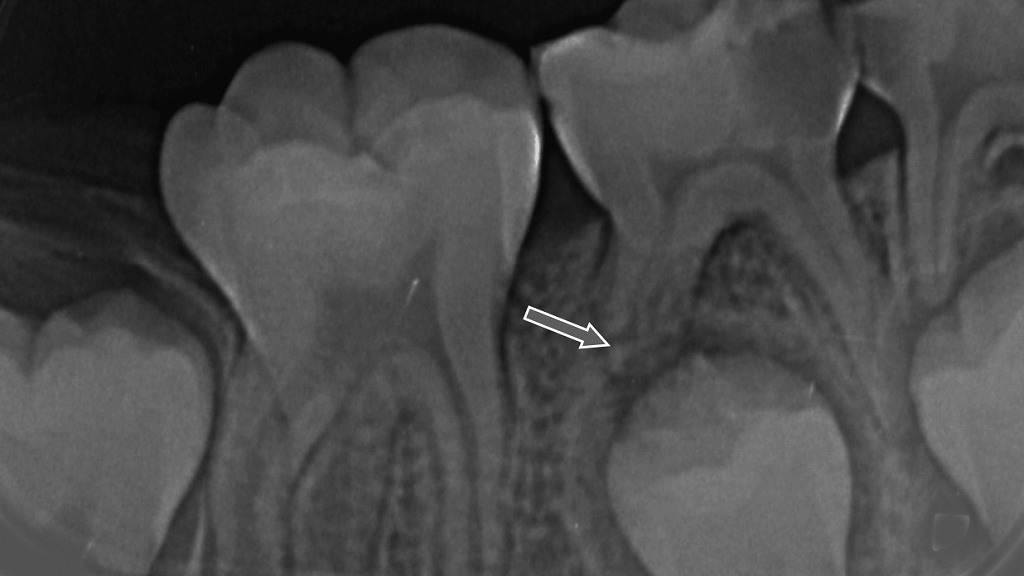

➤ 下顎E(乳歯)の歯根が、後方から萌出してくる第二小臼歯に押されて自然に吸収している状態

- 永久歯(この様X線では第二小臼歯)が萌出する際、

乳歯の歯根は自然に溶けて短くなる。 - これは正常な成長の一過程であり、痛みも腫れも起こらない。

- X線では、矢印部のように

乳歯の歯根が均一に短くなり、根尖から吸収されていく。

● 意味

- 永久歯が正しく生えてくるために必要な生理現象。

- 治療は不要で、自然に乳歯が抜ける。